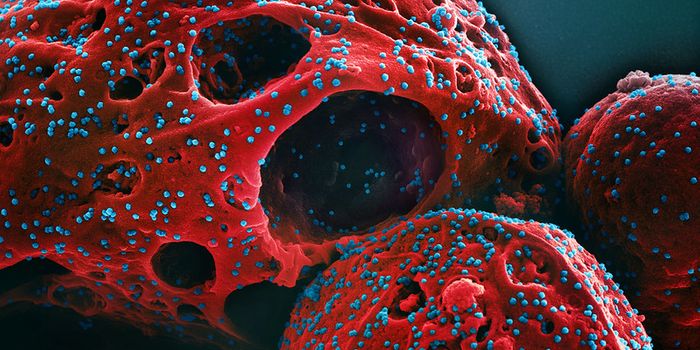

JUL 19, 2016CancerA decade-old technology to arm the immune system to fight cancer is now being adapted to fight HIV, one of the most pern ...

JUN 07, 2016ImmunologyThere’s a newfound hope in immunotherapies for cancer, and it’s a drug called nivolumab. On the market under ...

MAR 06, 2019Health & MedicineThere is a consensus that the first HIV infection occurred in the 1920s in Kinshasa, the Democratic Republic o ...